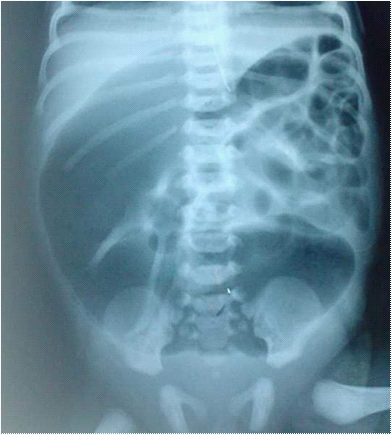

A girl weighing 3,050 Kg was delivered with a gestational age of 41 week. At the 2nd day of life she was admitted for neonatal occlusion with abdominal distension, bilious vomiting, and failure to pass meconium. Physical examination revealed a distended abdomen, no associated anomalies was founded. Abdominal X-Ray showed distended bowel, air fluid levels, with no air in the rectum (Figure 1). Surgical exploration was indicated and revealed a total colonic atresia (Type III) located at 3 cm below the Bauhin’s valve (Figure 2). Colostomy was made with proximal colic biopsy that indicate normal colic segment with presence of neuroganglionnary cells, colic continuity was restored 6months later with resection of a segment of the proximal dilated colon, with uneventful follow up.

Figure 1 Abdominal films with distended bowel.